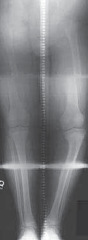

Chapter 30 Surgical Management of Blount’s Disease Eric D. Shirley and Richard S. Davidson DEFINITION Blount’…